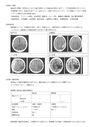

★理学療法・作業療法実習対策レポート★脳梗塞の基礎知識・評価項目について